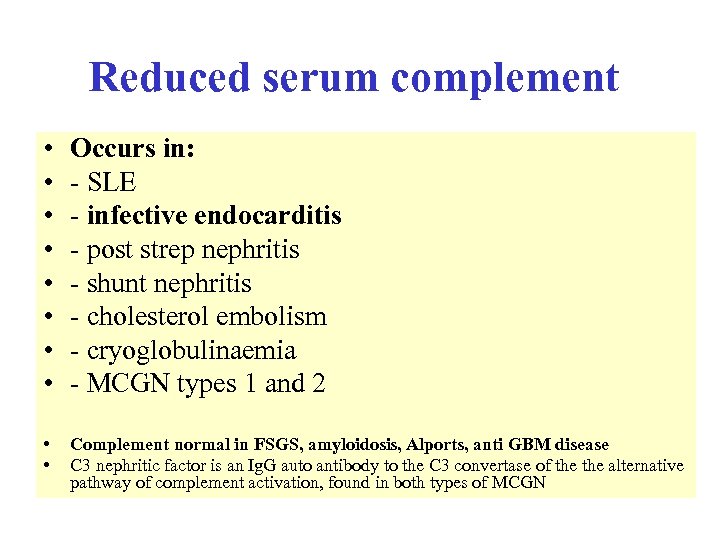

Reduced serum complement • • Occurs in: - SLE - infective endocarditis - post strep nephritis - shunt nephritis - cholesterol embolism - cryoglobulinaemia - MCGN types 1 and 2 • • Complement normal in FSGS, amyloidosis, Alports, anti GBM disease C 3 nephritic factor is an Ig. G auto antibody to the C 3 convertase of the alternative pathway of complement activation, found in both types of MCGN